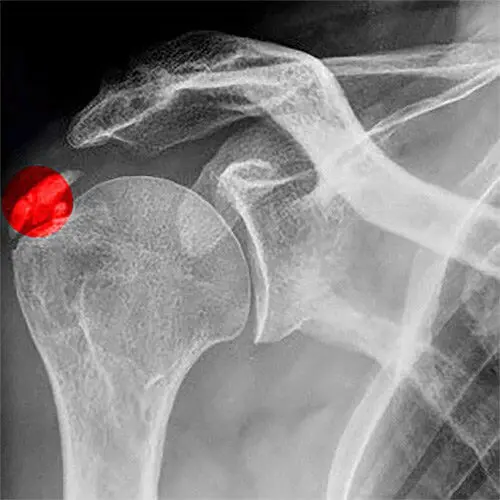

A tendinite calcária ocorre quando depósitos de cálcio se acumulam nos tendões do ombro, mais comumente no tendão do músculo supraespinal, que faz parte do manguito rotador. Esses depósitos podem variar de tamanho e, embora muitas pessoas possam não apresentar sintomas, muitas vezes eles causam dor intensa e restrição dos movimentos.

O diagnóstico da tendinite calcária geralmente é feito através de exames de imagem, como RX ou ultrassonografia, que podem mostrar claramente os depósitos de cálcio nos tendões. A avaliação clínica também é fundamental para determinar a gravidade dos sintomas e a limitação funcional do ombro.